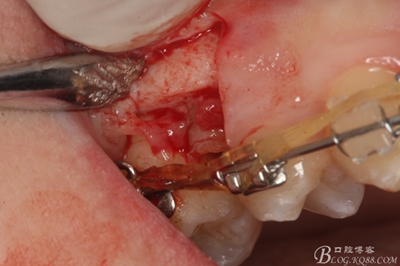

圖11.仔細(xì)考慮之后,在14頰側(cè)做垂直切口,切口長度僅達(dá)膜齦聯(lián)合處,做小切口。

圖12. 做垂直切口+齦溝內(nèi)切口,形成角形瓣,暴露出15根面。